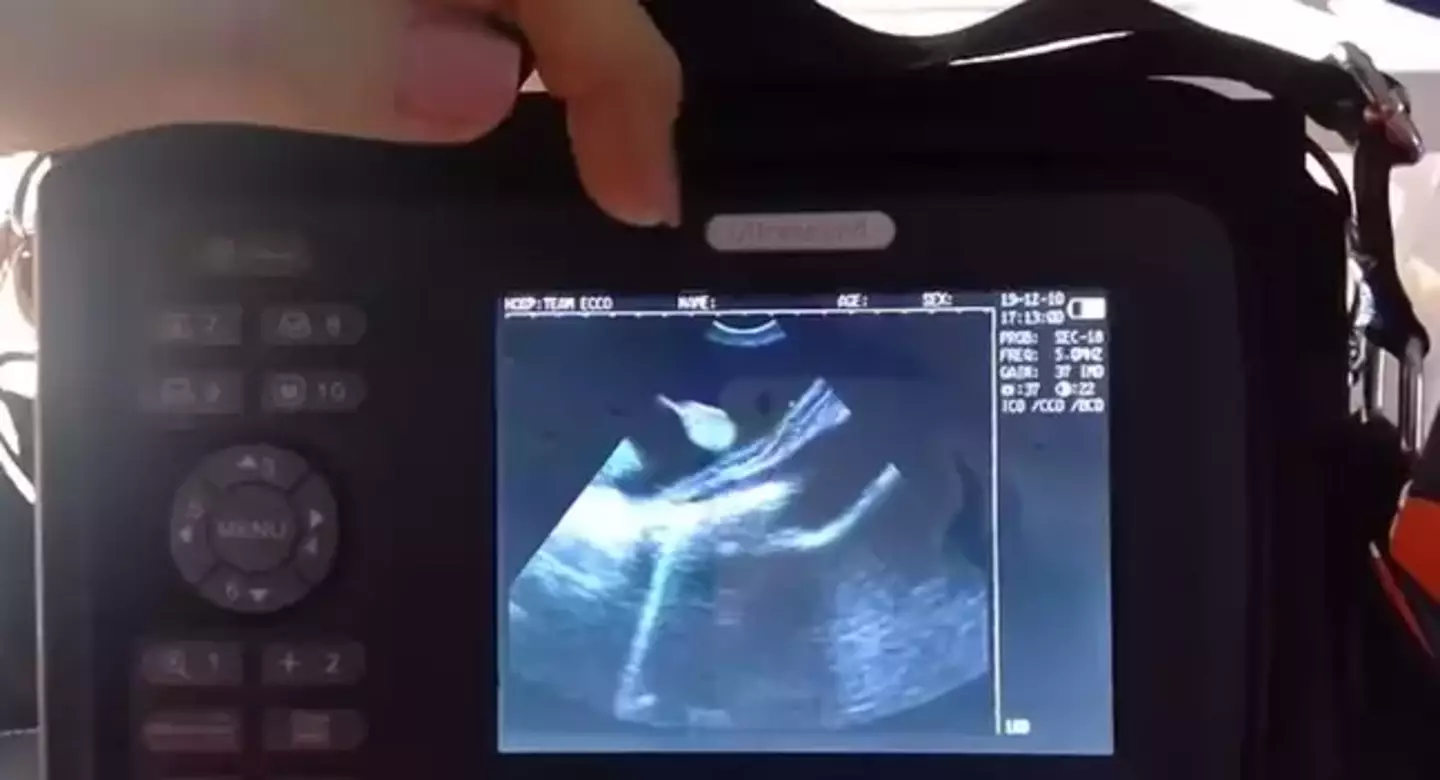

Deciding to carry out an ultrasound, they were shocked to discover that Charlotte was actually pregnant with up to four pups (that's what baby stingrays are called) and by now she's not far off the time to give birth.